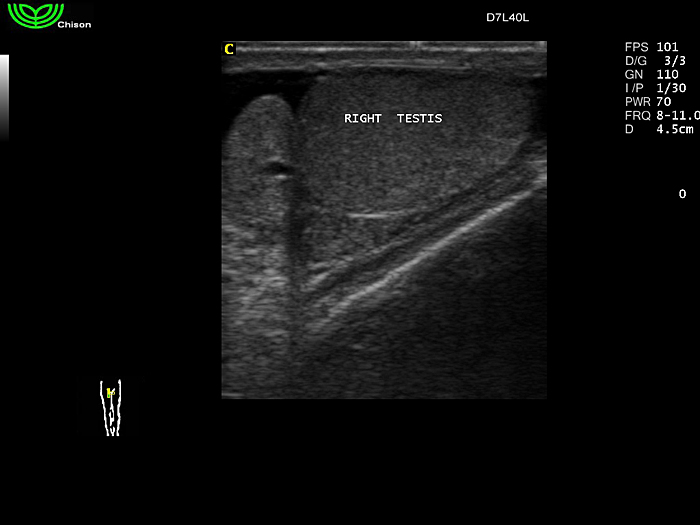

D7L40L 7.5МГц, линейный.

4.0МГц – 13.0 МГц. Применения: грудь, малые органы, нервы, сосуды, венозная катетеризация, мышцы и скелет, управление биопсией. |